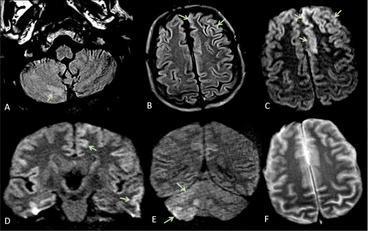

Il cervello, questo (per molti aspetti) sconosciuto (archivio unica.it)